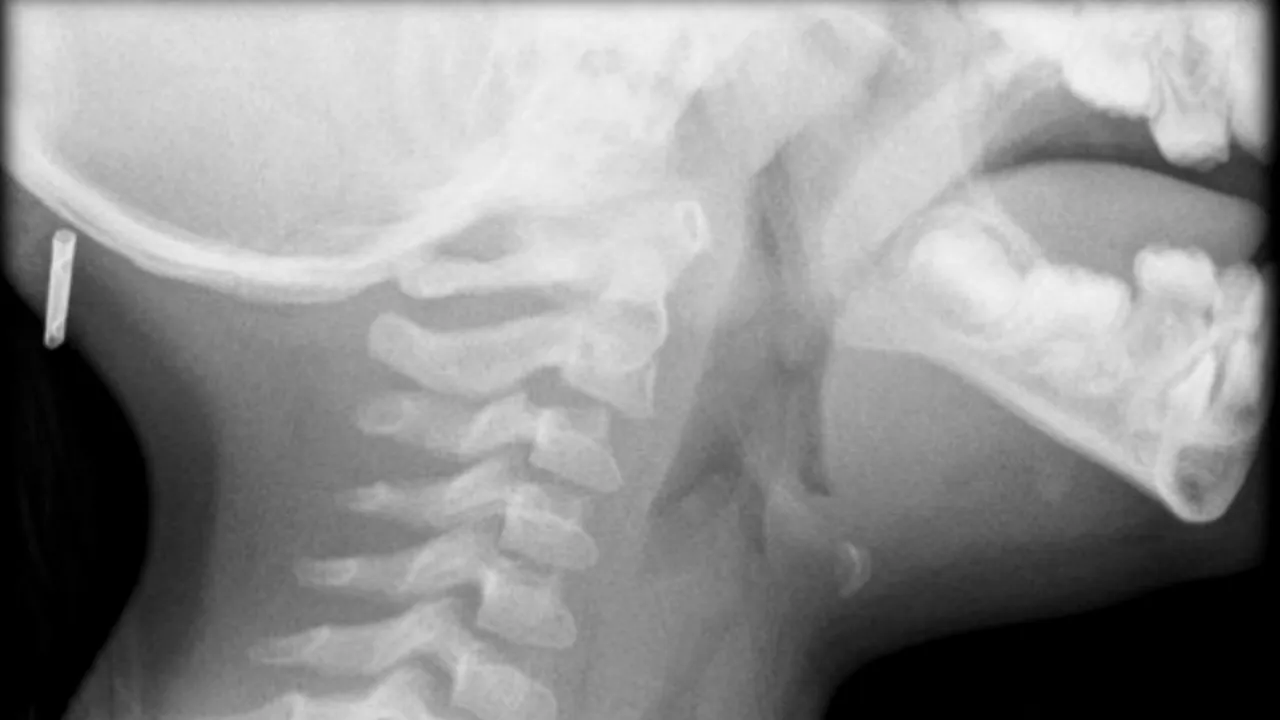

Tao Jiayuan, un tânăr de 16 ani din China, i-a șocat pe medici cu cazul său. Adolescentul se simțea rău de câteva zile. Acuza stări de vomă, era din ce în ce mai răgușit și tușea fără a fi răcit. Tânărul a ignorat toate aceste simptome până în momentul în care nu a mai putut să respire.

A fost transportat de urgență la medic. Doctorii au rămas șocați după ce l-au analizat. Tao avea în trahee o lipitoare, care trăia acolo de ceva vreme.

Ca să îi salveze viața, medicii au decis să îl opereze și să îi extragă lipitoarea din gât.

Astfel, adolescentul a fost supus unei operații care a durat 5 minute. În prezent, tânărul se simte bine.